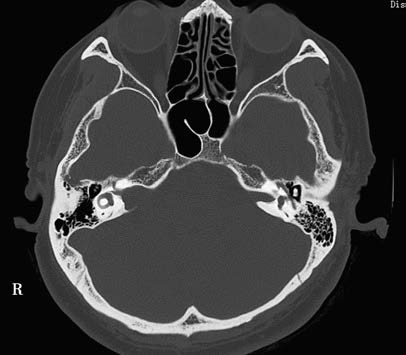

Imaging examinations include high-resolution CT of the temporal bone and enhanced MRI. The positivity rate of high-resolution CT is 60%–70%. CT typically reveals iso- or hypodense CPA mass lesions, often without calcification. Bone window CT may display widened and eroded internal auditory canals, with inhomogeneous enhancement after contrast administration. However, small tumors within the internal auditory canal (less than 5 mm) may be missed.

Figure 1 CT findings of acoustic neuroma in the temporal bone

The right internal auditory canal is enlarged, displaying a funnel-shaped appearance.